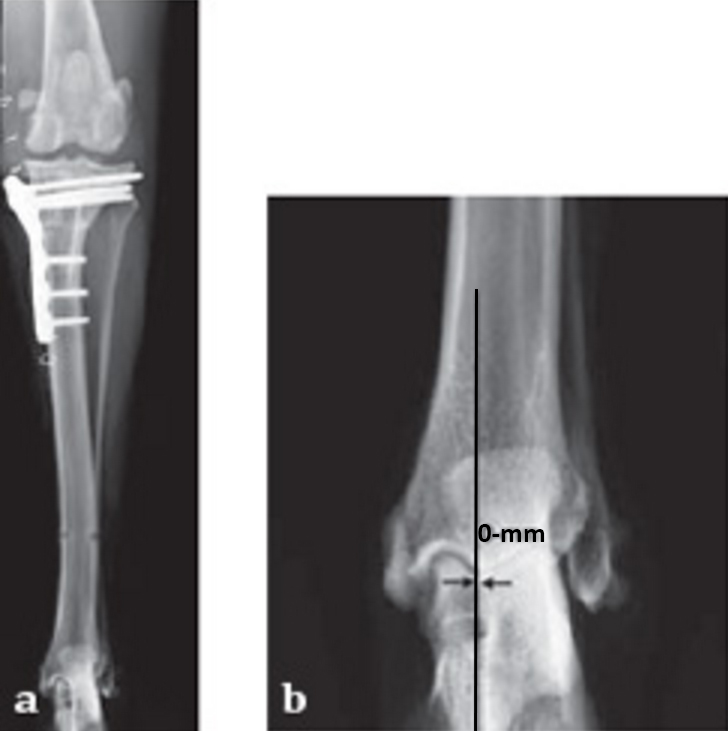

Case 1: Two-year-old Labrador Retriever

2-years-old Labrador Retriever, 30 kg, female. Chronic lameness in both hind limbs, chronic bilateral cranial cruciate ligament tears, with subsequent stifle joint instability and degenerative joint disease. At that time, she was more clinically lame on the left hind limb, and a surgical correction was subsequently performed on this limb. X-rays of the stifle joint revealed the degenerative joint changes and an effusion; the tibial plateau slope was 20. In addition, the x-rays confirmed that there was a slight amount of tibial torsion that also was observed clinically, accounting for a slight internal rotation of the distal limb. Radiographically, this could be assessed by a 4 mm shift of the normal point of intersection of the medial aspect of the calcaneus with the deepest point of the talar sulcus.

The stifle joint was surgically explored. All remaining remnants of the torn cranial cruciate ligament were debrided; in addition, the caudal pole of the medial meniscus was torn/crushed, and a partial meniscectomy of the damaged portion was performed. A TPLO plate 3.5 was applied to stabilize the fracture. The plate was applied in a neutral fashion. Postoperative x-rays revealed a tibial plateau angle of 5, and a correction of the torsion to 0 mm.

Follow-up x-rays at 8 weeks postoperatively revealed that the osteotomy had healed, and the dog was doing very well. The identical procedure was performed on the opposite stifle joint 2 months later. Healing was again obtained 8 weeks postoperative. Presently, the dog is about 1 year postoperatively and functioning very well.